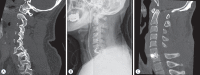

Methods: Twenty-three patients with single level cervical facet fracture and dislocation who were subjected to the anterior approach alone following immediate intraoperative reduction under general anesthesia from March 2013 to December 2017 were enrolled in this study. Neurological status, clinical outcome, and radiological studies were evaluated preoperatively, postoperatively, and during the follow-up period.

Results: The cohort comprised 15 men and eight women with a mean age of 57 years (from 24 to 81). All patients were operated on within the first 8 hours following the injury. After gentle manual reduction or closed reduction with Gardner-Wells traction, under general anesthesia monitored by somatosensory-evoked potentials, all operations were successfully completed using the anterior approach alone except in two patients, who had a risk of over-distraction. In them, a satisfactory gentle manual reduction or closed reduction was not possible, and required open posterior reduction of the locked facets followed by anterior cervical discectomy and fusion. In one patient, screw retropulsion was observed in 1 month after surgery. There were no reduction-related complications or neurological aggravations after surgery. All patients showed evidence of stability at the instrumented level at the final follow-up (mean follow-up, 12 months).

Conclusion: Anterior approach following intraoperative reduction monitored by somatosensory-evoked potentials under general anesthesia for cervical dislocation and locked facets is a relatively safe and effective alternative when cervical alignment is achieved by intraoperative reduction.